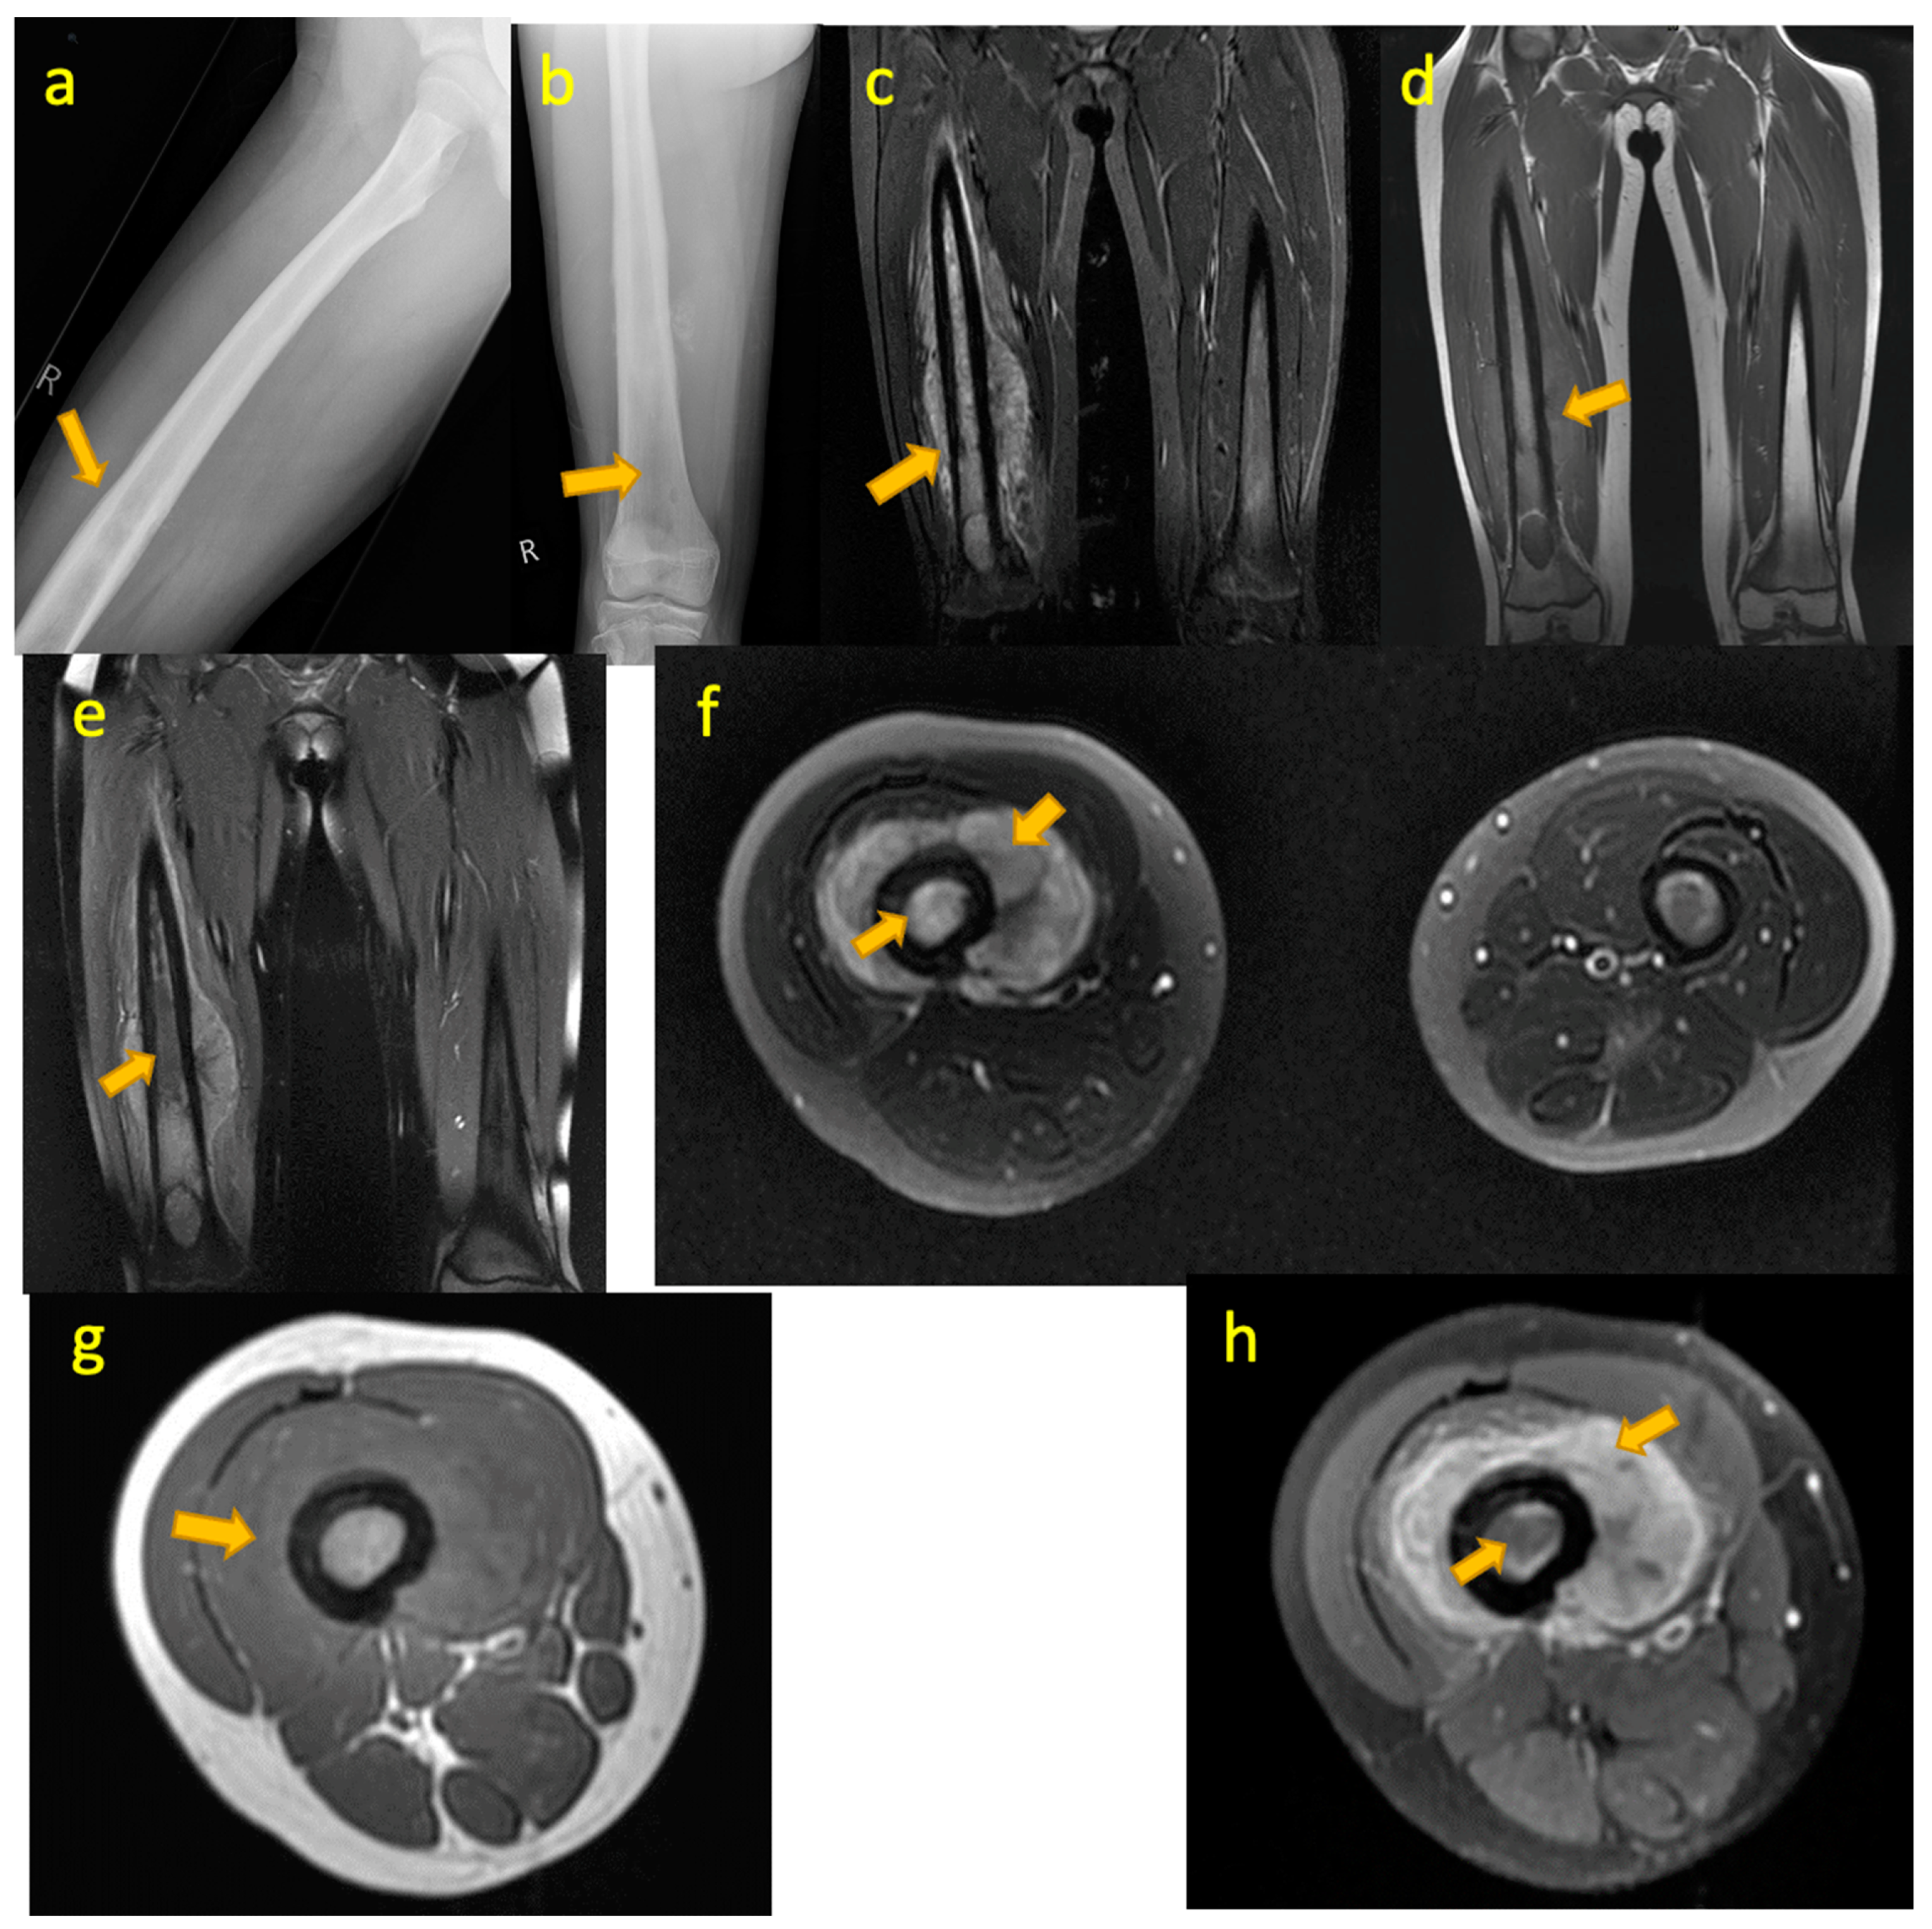

9. Ewing Sarcoma of Femur

10. Langerhans Cell Histiocytosis (LCH) Femur

11. Leukaemia

15. TB(Tuberculous) Pyomyositis Thigh